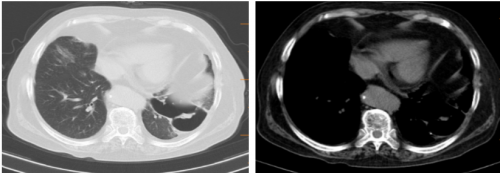

10月14日胸部CT检查:

10月15日

10-20胸部CT: